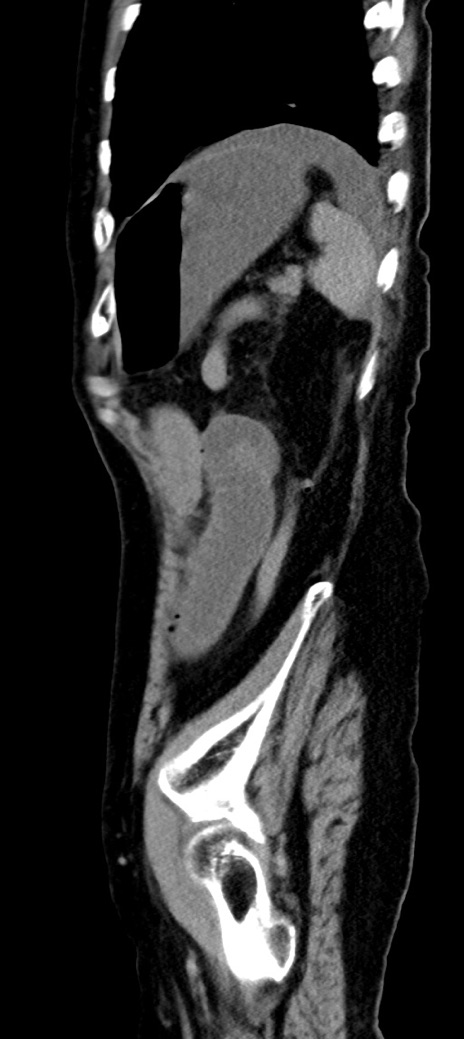

症例40(矢状断像)他院1日前

【症例】90歳代女性

【主訴】腹痛・嘔吐

【現病歴】 食欲低下、嘔吐があり昨日他院受診。肺炎と診断され入院となる。入院後より腹部全体に圧痛あり。胃管留置され経過みていたが、症状持続するため、

当院転院となる。

【既往歴】胸椎圧迫骨折、胆石症

【身体所見】腹部:中央に激痛あり、圧痛あり、反跳痛不明

【データ】WBC 17100、CRP 18.82